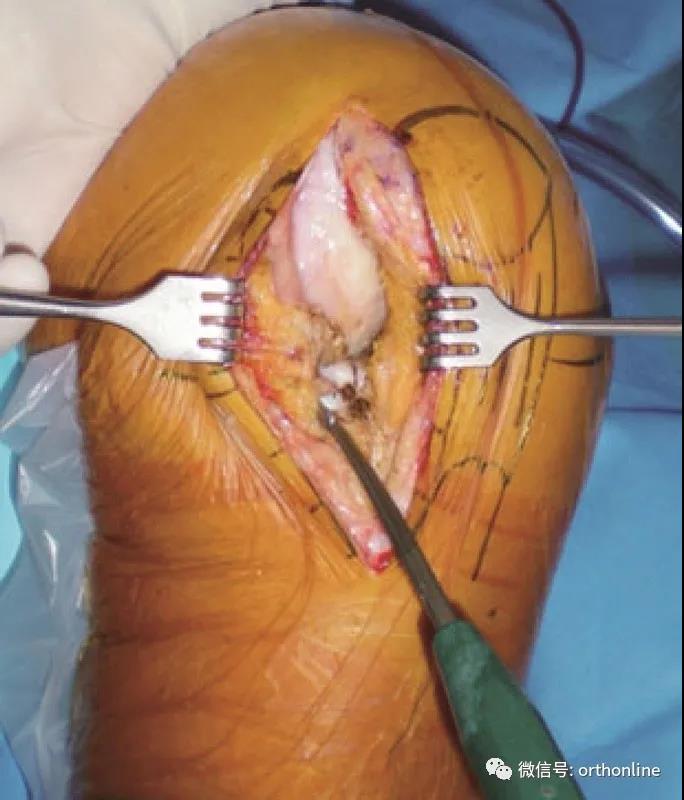

切口暴露

胫骨截骨

胫骨水平截骨垂直力线,纵截骨沿股骨外侧髁的内缘